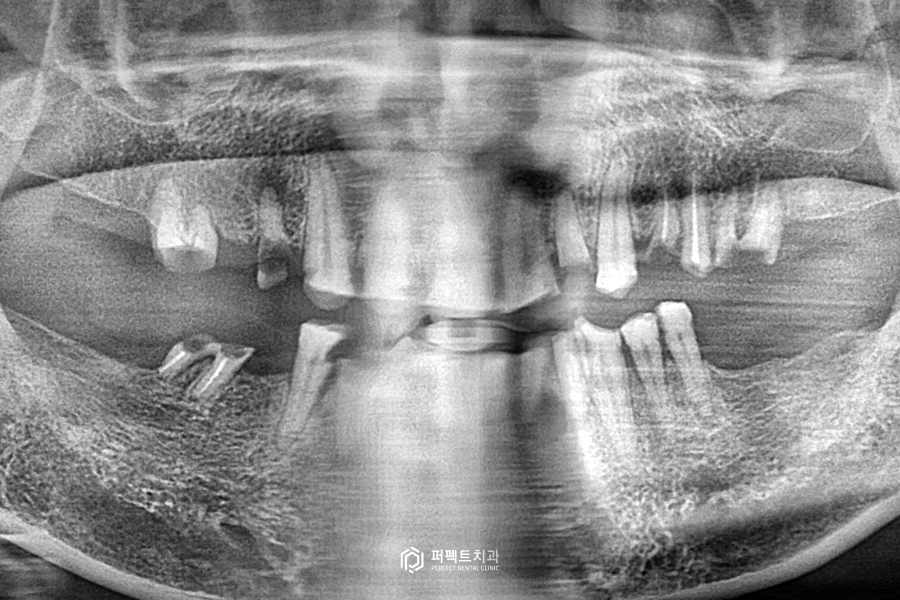

초진 엑스레이

처음 오셨을 때 엑스레이 사진을 보시면 엑스레이 사진만 보아도 남아있는 치아가 닳고 깨져있어 멀쩡한 치아가 없어 보입니다.